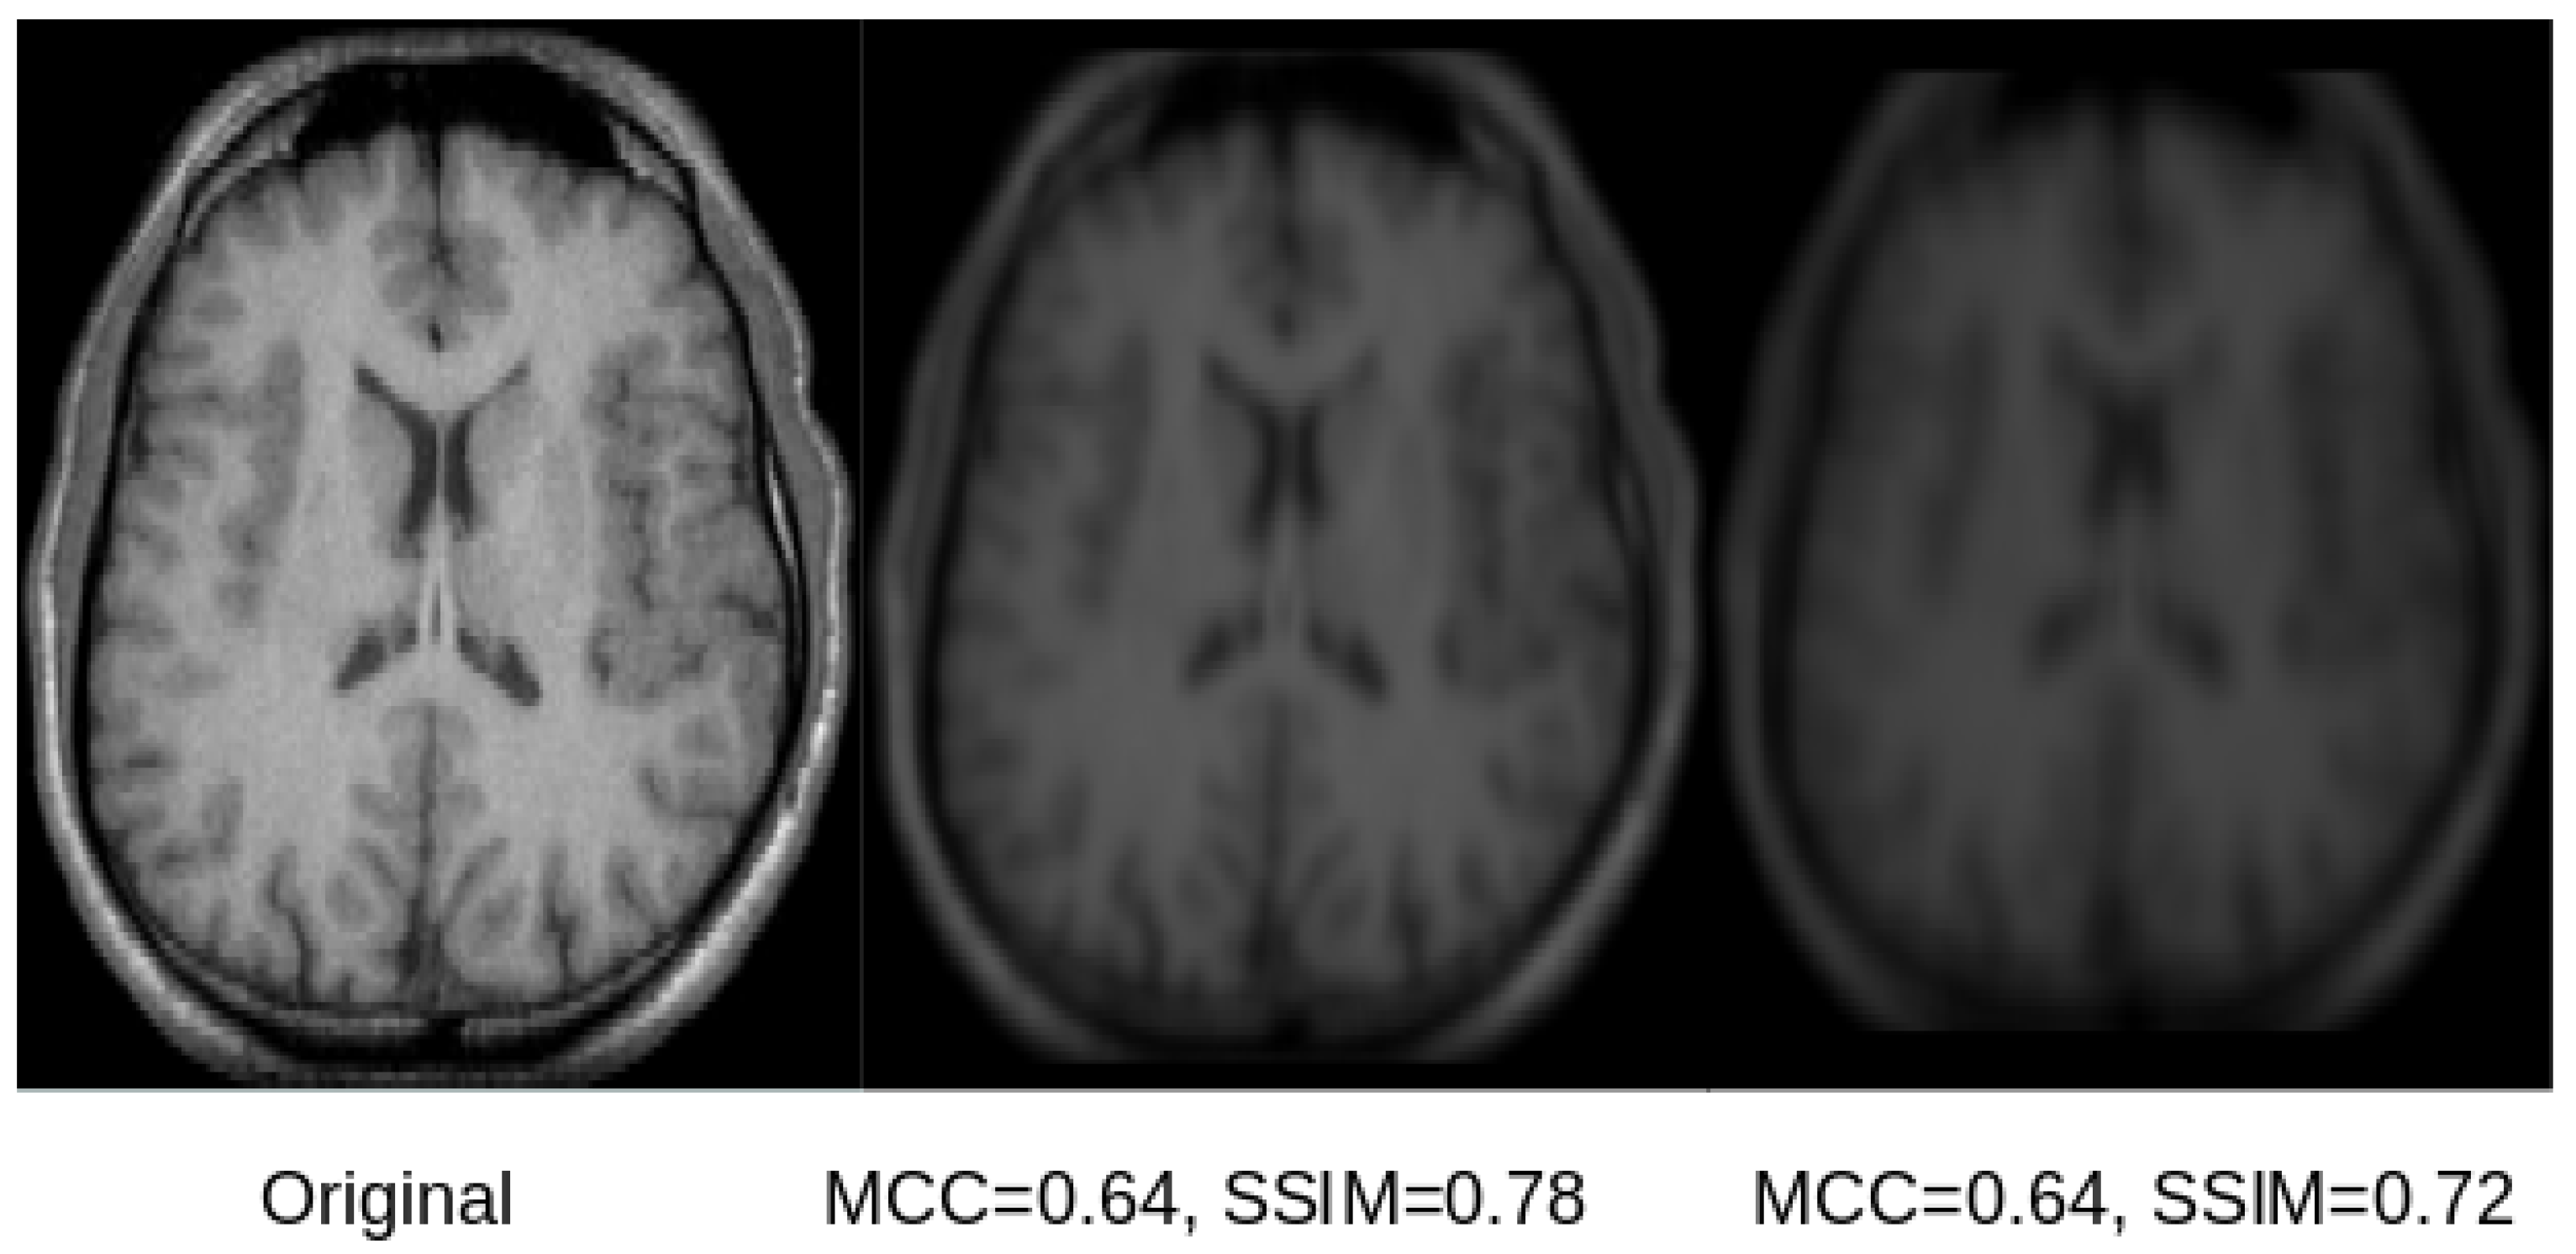

Exemplary qualitative results for U-Net and SegNet-based reconstructions for the skull-stripped and original images are shown in Figure 5 and Figure 6, respectively. Those results indicate that both SSIM and MCC in general reflect the visual quality of the reconstructed image in comparison to the original image. Both measures assign higher values to visually better reconstructions that are less blurry. However, the SSIM metric appears better suited and more sensitive to image blurring, making it the better metric for this purpose.

Figure 5.

The original skull-stripped image (left) and the corresponding reconstruction from the latent space of the U-Net (center) and SegNet (right) for three different subjects. For the subject shown in the top row, the reconstructions are sharp and there is only a scaling difference between the original and the reconstructed images. In case of the SegNet reconstruction, some minor blurring can be seen. For the subject shown in the middle row, the reconstructions show some significant degradation due to blurring, but they are still clear and recognizable. For the subject shown in the bottom row, the reconstructions show severe blurring. The corresponding SSIM and MCC scores reflect those qualitative impressions, whereas the SSIM seems generally better suited and more sensitive.

Figure 6.

A selected slice from an original MRI dataset without skull stripping (left) and its reconstruction from the latent space of the U-Net (center) and SegNet (right). As can be observed in the image, the original and the reconstructed images are overall similar. However, the reconstruction from the SegNet model is more blurry, which is reflected by lower a SSIM score, while the MCC is very similar for both reconstructions, not reflecting the differences in reconstruction quality.

Based on the visual results exemplified in Figure 5 and Figure 6, it can be concluded that all reconstructions show some degree of blurriness. The overall reconstruction quality including the blurriness is best reflected in the SSIM scores, which range between and . Overall, the results of this study show that reconstruction of the original images used for training of CNN models is possible, but is accompanied by some amount of blurring. This finding is also in line with the results from model inversion attack studies in computer vision [8]. The results of this study also suggest that the reconstructions from the U-Net are better than those for the SegNet. A potential reason for this finding could be the skip-connections of the U-Net.